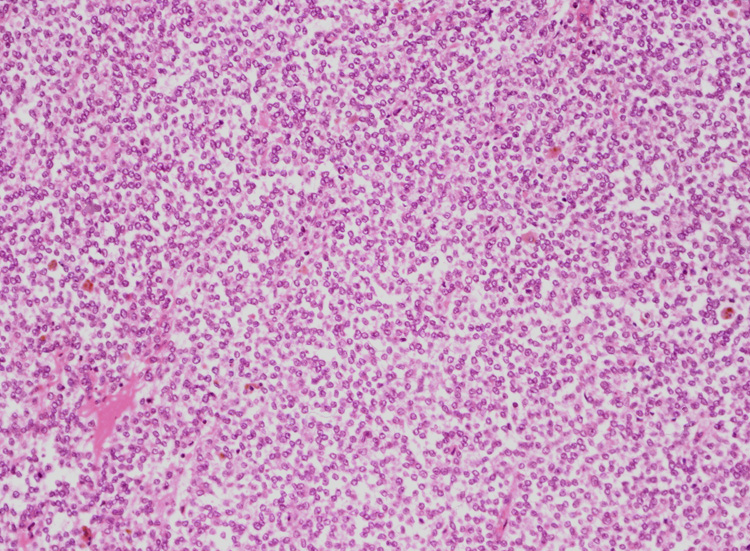

ルーペ像では(Fig.01)ヘモジデリンを貪食したマクロファージに富む線維性間質をもち、腫瘍細胞が胞巣状, 地図状に増殖している。線維性間質はdesmoplasticではなく成熟した線維組織のようである。本例ではさらに腫瘍胞巣内にタンパク液の貯留した偽嚢胞様構造が散在するほか、層状の腫瘍細胞に裏装された嚢胞様構造が出現している。(Fig.03,04)

腫瘍細胞はシート状密に増殖する、類円形小型淡明な核をもった細胞質の乏しい細胞からなる。細胞分裂像は目立たなかった。(Fig.05,06), 線維間質部分の拡大所見。腫瘍細胞が小さな集簇をつくって浸潤している。(Fig.07) Fig08では血管周囲性ロゼットが認められる。